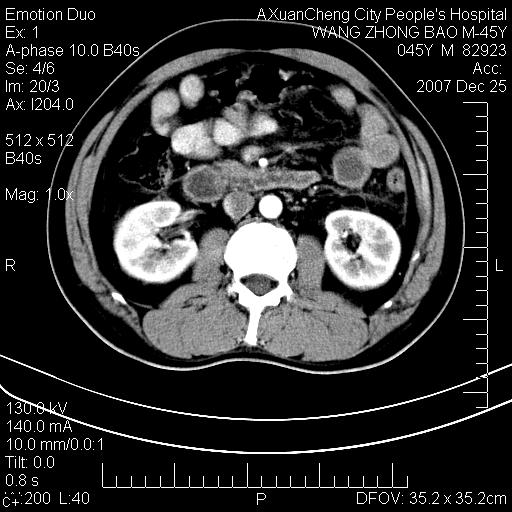

以下是引用卜一在2007-12-25 14:07:00的发言:[br]胰头钩部略增大,与十二指肠壶腹部关系密切,其内明显见软组织密度肿块,明显强化,但肠壁较光滑 柔软。考虑:炎性增生!建议消炎后复查!待除外壶腹部腺癌!

以下是引用zjzjr在2007-12-25 13:35:00的发言:[br]考虑正常的十二指肠乳头部,建议胃镜检查.

以下是引用qiuleiyu在2007-12-25 18:14:00的发言:[br]胰腺增大,周边渗出改变,肾前筋膜明显增厚,示少量积液.胆囊壁毛糙,周边少许渗出,胆总管壁厚,异常强化,然扩张不明显.结合病程急短;考虑;胆管炎,胆囊炎,胆源性胰腺炎可能大,请结合实验室检查及随访.

以下是引用lisihao在2007-12-25 14:23:00的发言:[br]急性水肿型胰腺炎[br]依据:1、胰腺弥漫性肿大,边缘稍毛糙;[br] 2、双侧肾周筋膜增厚,尤以左侧为甚(重要征象)[br] 3、双侧后胸膜增厚(刺激性炎症);[br] 4、结合病史,查血尿淀粉酶应该可以确诊。